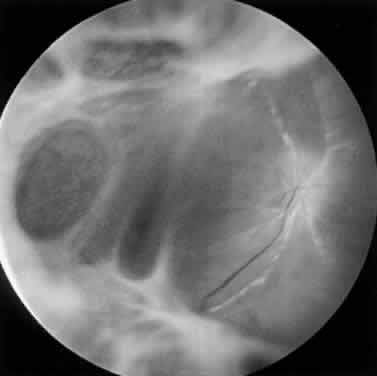

Intravenous fluorescein angiography may be helpful in delineating the extent of infection and elucidating the cause of central visual loss. In the early frames, choroidal perfusion defects may be seen; these defects are caused by areas of focal choroidal inflammatory cell accumulation and overlying retinal pigment epithelial damage (Fig. 16). Such choroidal perfusion defects may occur away from zones of active necrosis.42 Acute obstruction of the central retinal artery or any of its branches may be present. Peripheral views in the areas of active retinitis commonly show little or no intravascular fluorescein in the retinal arteries and veins. Often an abrupt “cut-off” of the intravascular fluorescein may be apparent at the edges of the retinal inflammation (see Fig. 4B and C). Areas of active retinitis show blockage of the underlying choroidal fluorescein pattern (see Fig. 7B). Recirculation phase views may reveal macular leakage, optic disc, and retinal vasculature staining.

Fig. 16. Fluorescein angiogram during early venous phase of active ARN syndrome showing choroidal blocking defects secondary to choroidal involvement.